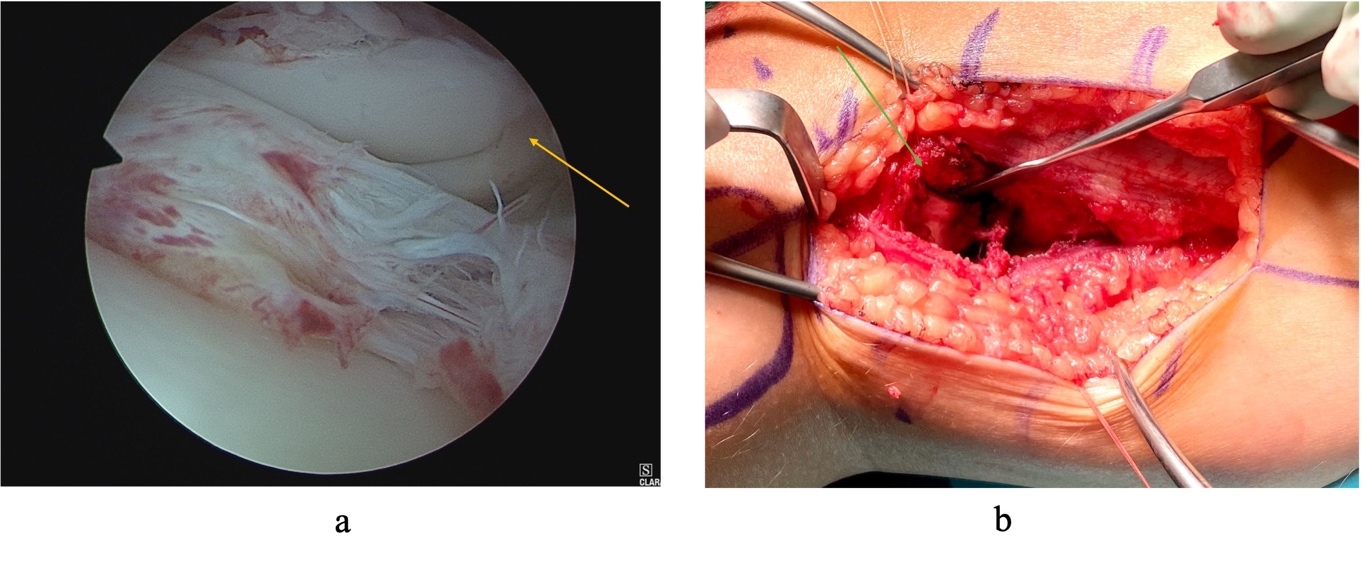

Arthroscopy also revealed an area of chondral damage, at the level of the fracture line, for which micro-fracturing was performed. Reassessment of the patients ROM revealed flexion to 130° with an FFD of only 20°. Closure was performed in consecutive layers and the patient was placed in a hinged knee brace locked in 30° flexion. Postoperatively, the patient remained non-weight bearing for approximately six weeks with range of motion exercises starting two weeks post procedure. At five-month follow up this patient had full ROM and was mobilizing pain-free. She had returned to all regular daily activities including running and jumping comfortably. On examination there was no leg length discrepancy or angular deformity, and ROM was fully restored (0° to 140°) (Fig 5). Radiographs at 7 months postoperatively showed good alignment with no obvious physeal injury (Fig 5).